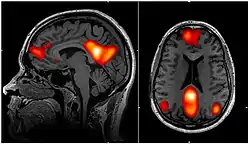

Functional connectivity refers to the functionally integrated relationship between spatially separated brain regions. Unlike structural connectivity which looks for physical connections in the brain, functional connectivity is related to similar patterns of activation in different brain regions regardless of the apparent physical connectedness of the regions.[1] This type of connectivity was discovered in the mid-1990s and has been seen primarily using fMRI and Positron emission tomography.[2] Functional connectivity is usually measured during resting state fMRI and is typically analyzed in terms of correlation, coherence, and spatial grouping based on temporal similarities.[3] These methods have been used to show that functional connectivity is related to behavior in a variety of different tasks, and that it has a neural basis. These methods assume the functional connections in the brain remain constant in a short time over a task or period of data collection.

The default mode network above is one example of a brain network seen using steady state connectivity. This network is fairly stable in time, but it has been shown to have a variable relationship with other networks, and to vary slightly in its own characteristics in time.